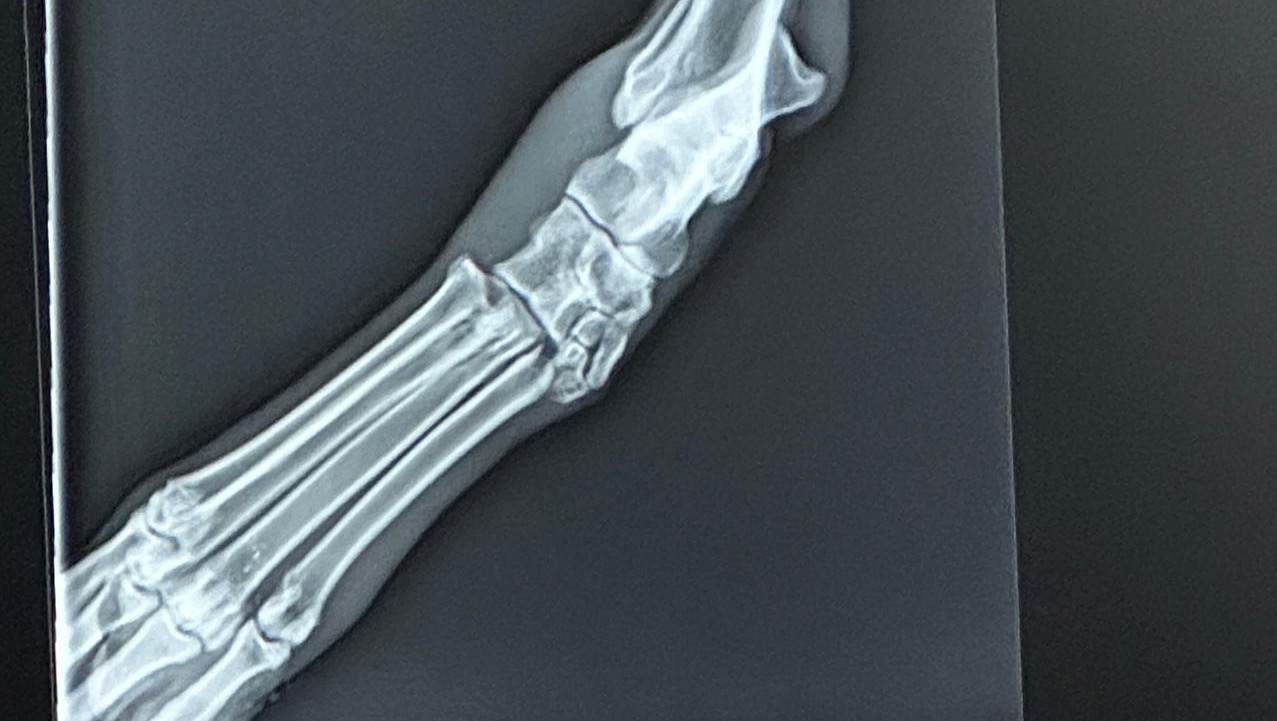

Unfortunately, over the weekend, Penelope suffered a devastating injury when she dislocated her toe. After seeing our trusted veterinarian, Dr. Gripp in Hico, TX, Penelope was referred to the expert team at I-20 Emergency Animal Hospital in Weatherford, TX.

It became clear that she needed specialized care, and she was ultimately sent to the renowned DVSC Orthopedic Surgeons in Fort Worth. They have recommended surgery and specialized post-surgery physical therapy to ensure a full recovery, which is estimated to cost around $13,800.